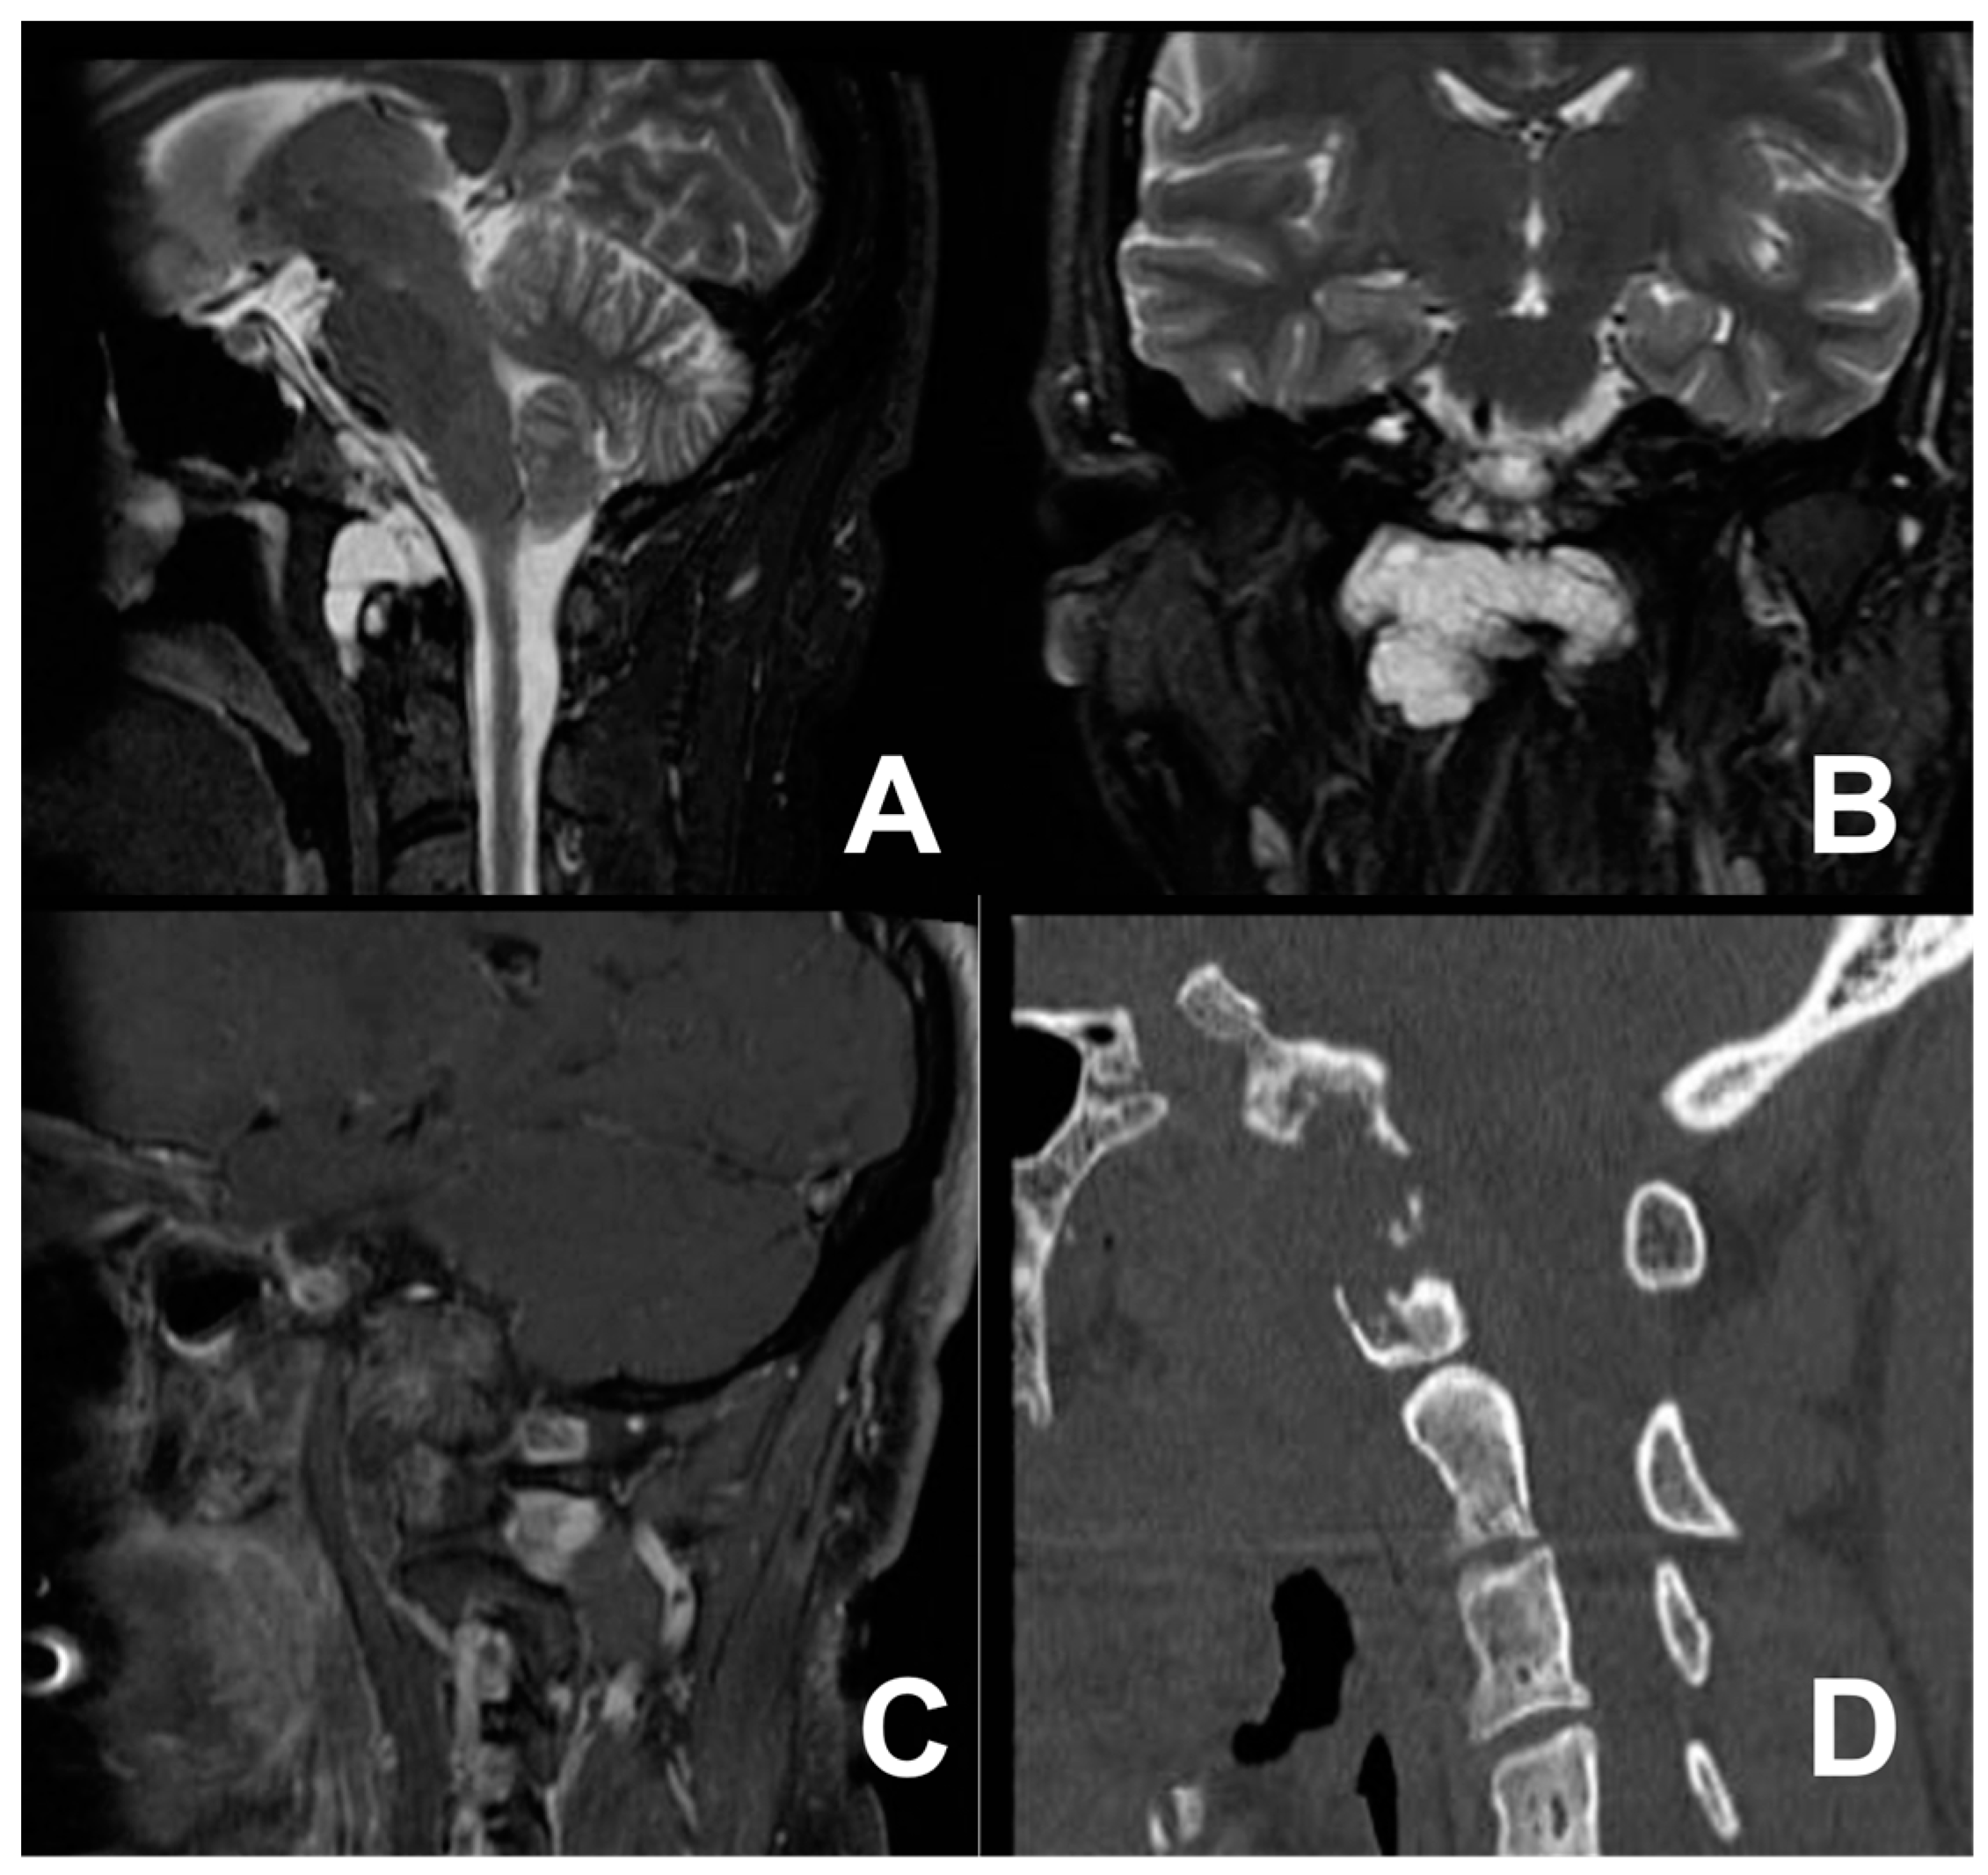

Figure 2.

T2-weighted MRI scan in the sagittal (A) and coronal views (B) and T1 sagittal post-contrast image (C) showing the cervical tumor anteriorly extending toward the occipital condyles, involving the right anterior arch of the atlas, with spongy bone replacement and consequential destruction of the cortical and right side of the clivus (D).